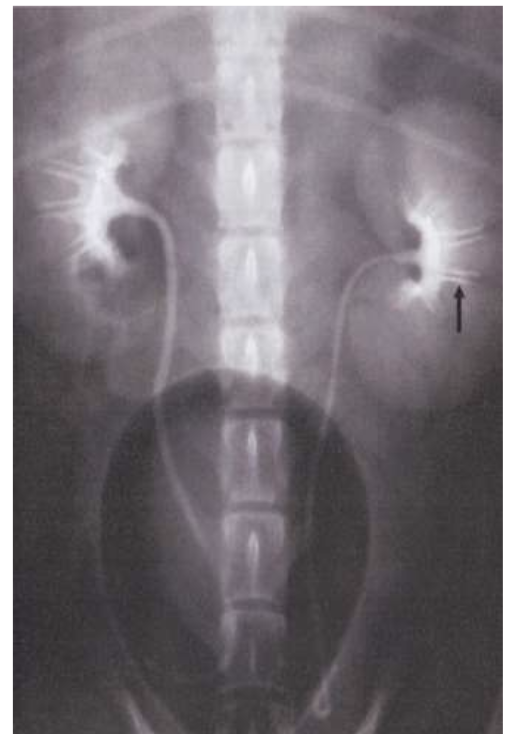

Label the renal cortex cross section (cat)

what is this?

Renal pelvic recess